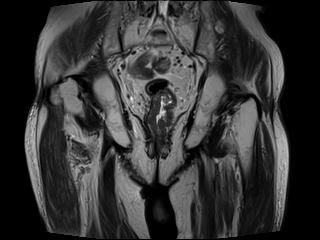

上圖為直腸癌術(shù)后復(fù)發(fā)患者。